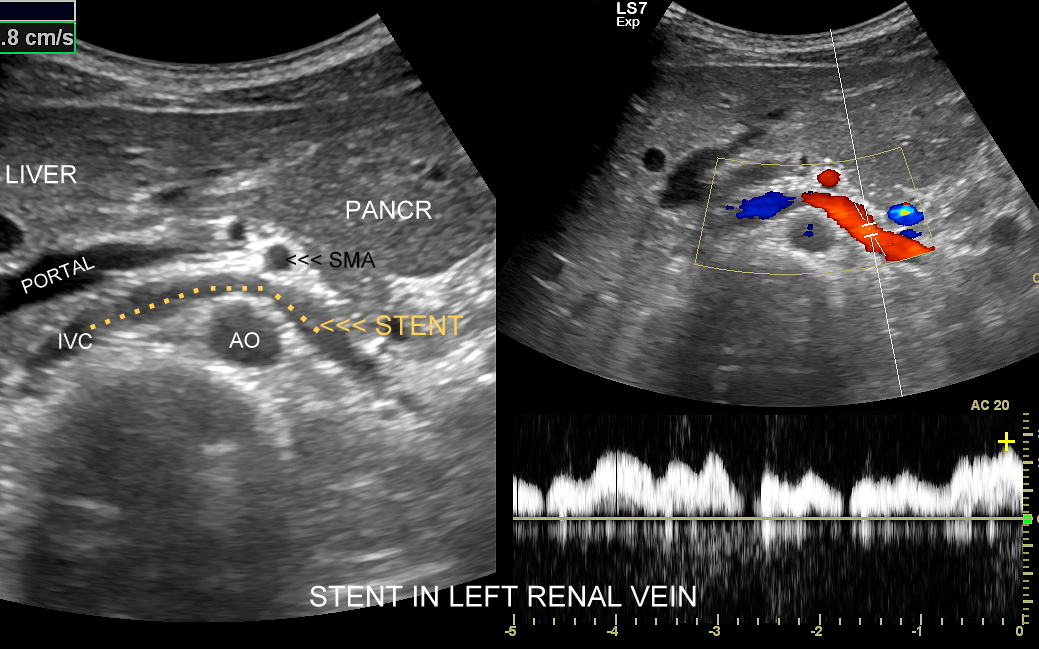

Badanie USG żył kończyn dolnych najczęściej wykonywane jest w ramach diagnostyki niewydolności żył powierzchownych oraz ich objawów w postaci pajączków żylnych, żylaków kończyn dolnych, obrzęków i owrzodzeń żylnych. Kolejnym pod względem częstości wskazaniem do badania Doppler żył jest podejrzenie zakrzepicy żył głębokich kończyn dolnych, monitorowanie leczenia zakrzepicy oraz ocena jej powikłań odległych. Powikłaniem nieleczonej zakrzepicy żył głębokich może być zespół pozakrzepowy manifestujący się masywnymi obrzękami kończyny i zaburzeniami troficznymi. Badanie USG Doppler żył kończyn dolnych często uzupełniane jest oceną układu żył centralnych w miednicy i jamie brzusznej. W tych obszarach również pojawiać się mogą żylne zmiany zakrzepowe, niedrożności żył, a nawet zmiany nowotworowe.

Podczas najczęściej przeprowadzanego badania, tj. USG Doppler kończyn dolnych, oceniane są żyły głębokie oraz powierzchowne na całej długości kończyny – od stóp aż do pachwiny. Czasami mogą zaistnieć wskazania do rozszerzenia badania na wyższy poziom układu żylnego, tj. na żyły biodrowe w miednicy i żyłę główną dolną w jamie brzusznej. Badanie USG żył jest badaniem dynamicznym, tzn. oprócz oceny wyglądu żył wykonuje się różnorodne próby czynnościowe, takie jak kompresja, głębokie oddychanie, próba Valsavy, podczas których rejestruje się przepływy krwi w żyłach.

Interdyscyplinarna Pracownia USG dr Tomasza Szczepańskiego to instytucja przełomowa na gruncie Polski i Europy. W ramach jej działania od 2011 r. wprowadzonych zostało do polskiej medycyny wiele innowacyjnych rozwiązań, w tym badania MPUS jamy brzusznej, USG wątroby z kontrastem CEUS, USG skóry i tkanek miękkich, USG twarzy, a także kompleksowy przegląd zdrowia realizowany przy użyciu zaawansowanego technologicznie sprzętu USG. Dr Szczepański umożliwił mieszkańcom Wrocławia dostęp do pełnej gamy badań dopplerowskich, w tym badania USG narządów przeszczepionych. Jako pierwszy w Polsce wykonał śródoperacyjne badanie CEUS przy operacji nerki. Sprawdź więcej:

USG PRZEPŁYWY NERKOWE >